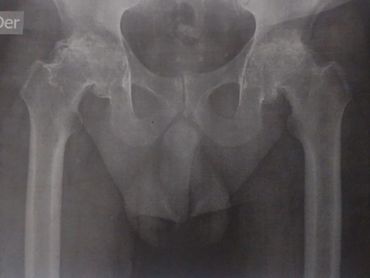

Artroplastía total de cadera bilateral en un tiempo quirúrgico